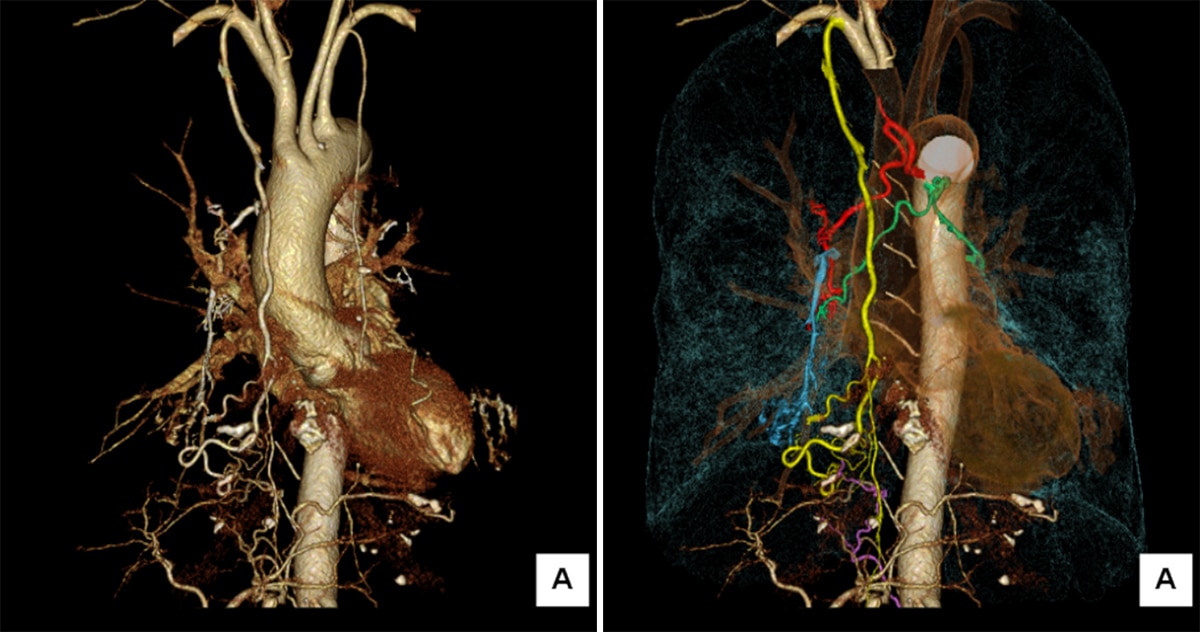

図2 6相目の3D再構成

右は必要な血管を色分けして表示している

黄:右内胸動脈、赤:右気管支動脈、緑:左気管支動脈から分岐する右気管支動脈、紫:右下横隔動脈、青:肺動脈 (右A5) への造影剤の逆流